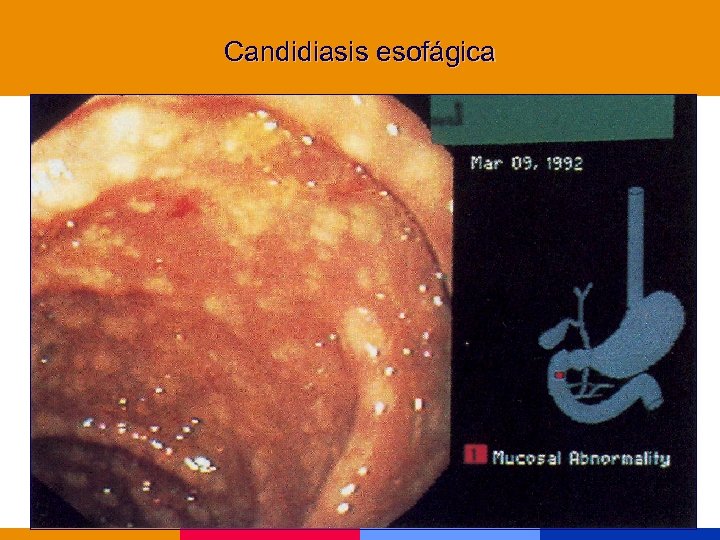

Candidiasis esofágica

Candidiasis esofágica